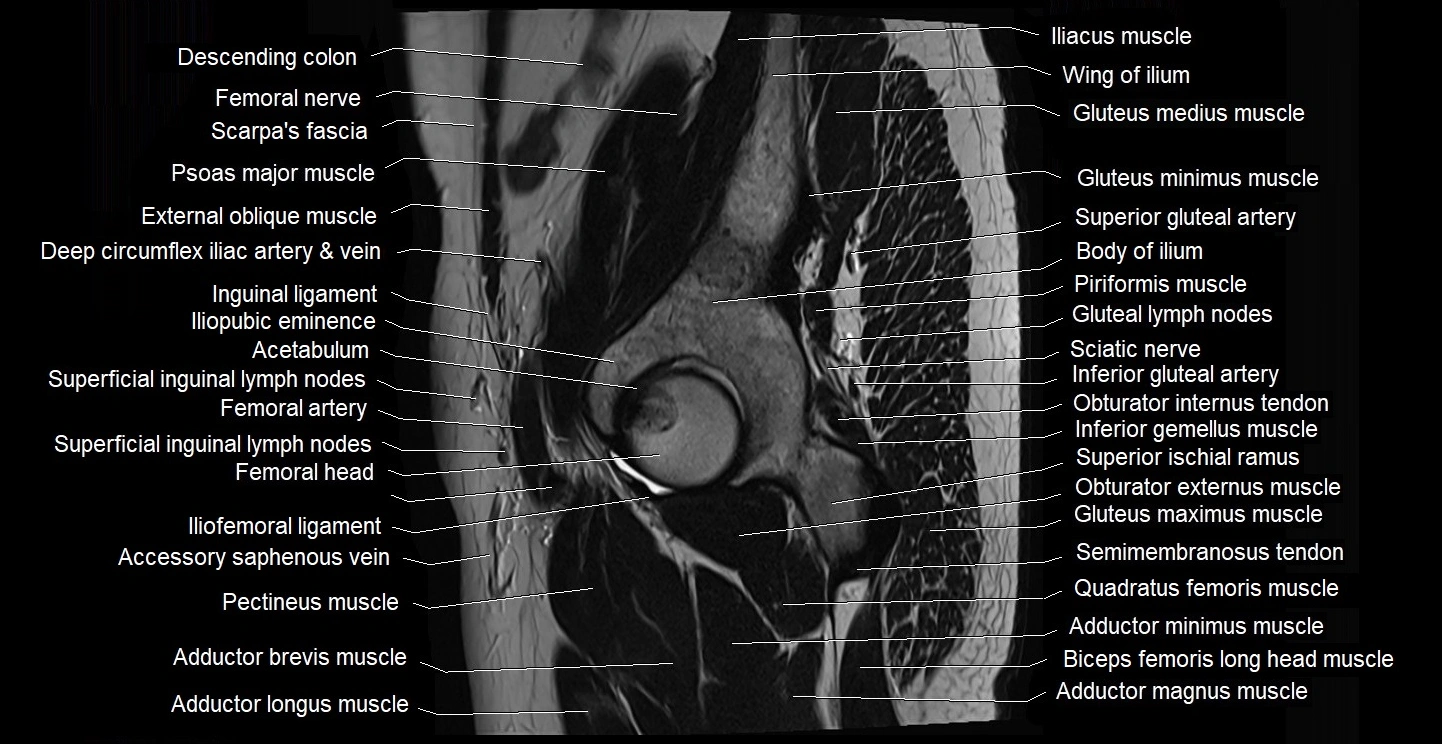

- Acetabulum

- Body of ilium

- Femoral nerve

- Gluteal lymph nodes

- Gluteus maximus muscle

- Gluteus medius muscle

- Gluteus minimus muscle

- Head of femur

- Iliofemoral ligament

- Iliopsoas muscle

- Iliopsoas tendon

- Iliopubic eminence

- Inferior gemellus muscle

- Inferior gluteal artery

- Inferior pubic ramus

- Inguinal ligament

- Pectineus muscle

- Pedicle of vertebra

- Piriformis muscle

- Psoas major muscle

- Quadratus femoris muscle

- Rectus femoris muscle

- Sartorius muscle

- Sciatic nerve

- Semimembranosus tendon (proximal)

- Superficial inguinal lymph nodes

- Superior gluteal artery

- Tensor fasciae latae muscle